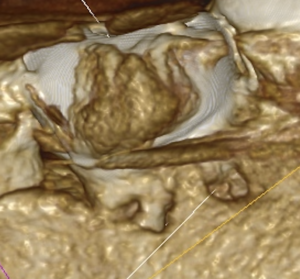

この歯は歯頸部に外部吸収を抱えていたのである。

私が気づいたのは、

この絵をみて

違和感

を感じたからである。

穿孔しているのだろうか?とまず思ったが、CBCTをみてそれは穿孔でなく外部吸収の可能性が高いと判断できた。

そしてそれを行う前に外部吸収を封鎖する必要がある。

1. まず外部吸収を封鎖する

2. その後(その日に)、再根管治療を行う

M根の吸収部位を明示した。

そして、キャビトンを置いてBC Linerで外部吸収部位を閉鎖した。

Dも同様にして閉鎖し、双方とも研磨し、縫合した。